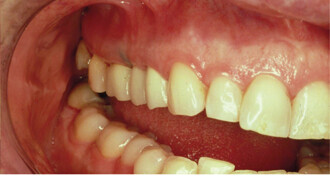

Biomechanics in the orthodontic treatment of complex multidisciplinary problems

In recent years, the purview of orthodontics has grown to include an increasing number of adult patients, many of whom present with complex malocclusions ...